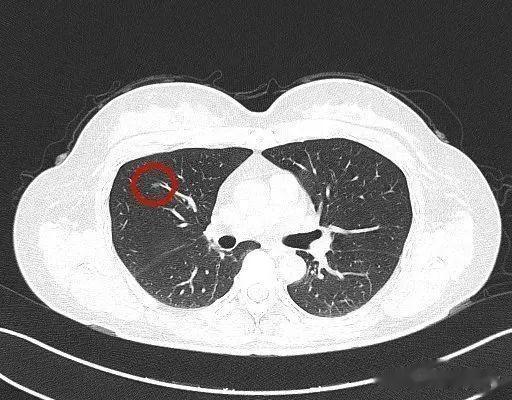

我们先看当时提供的2018年的主病灶影像(2017年发现 , 但没有电子版的影像图像):

左下叶磨玻璃结节 , 有血管穿行 , 整体轮廓与瘤肺边界清楚 , 表面略不平 , 密度稍不均 , 但显著的实性成分不太明显 。